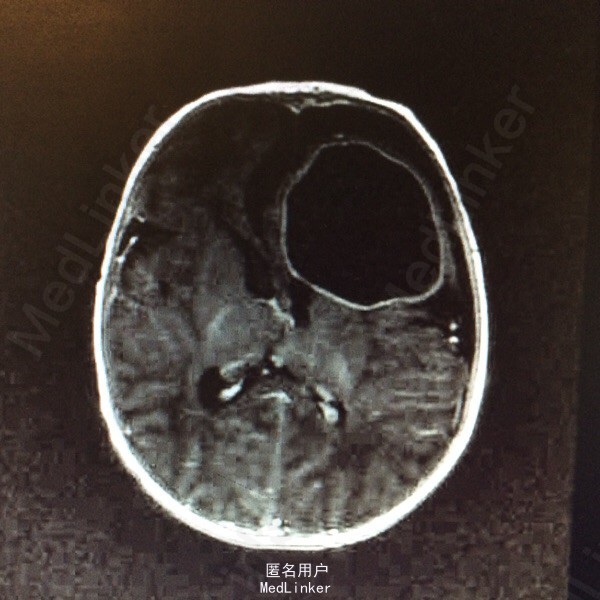

血常规:白细胞计数 WBC 18.61*10~9/L,中性粒细胞比例 Neu% 47.5%,淋巴细胞比例 Lym% 40.3%,血红蛋白 HGB 115g/L,血小板计数 PLT 433*10~9/L,CRP 79mg/L。大小便常规基本正常。肝肾功血糖心肌酶谱基本正常。降钙素原定量 PCT 1.80ng/ml。脑脊液生化 蛋白质 M-TP 528.1mg/灯笼,氯化物 CL 111.5mmol/L,葡萄糖 GLU 0.19mmol/L。 脑脊液常规检查(CSF) 细胞总数 110516.0×10~6/L,白细胞计数 108500.0×10~6/L,红细胞计数 2016×10~6/L,直接分类-单个核细胞比例 45%,直接分类-多核细胞比例 55%,颜色 黄色,透明度 浑浊,蛋白定性(Pandy's) 阳性(2+)。胸片:双肺改变考虑炎变,建议治疗后复查。颅内(彩超) :左侧脑实质囊性占位。磁共振增强扫描颅脑 :1、左侧额叶较大混杂信号囊状影,增强扫描壁明显强化,考虑脑脓肿;伴额、颞部蛛网膜下腔积液,请结合临床及其它检查。2、左侧侧脑室后角旁小结节影,增强扫描环形强化,考虑小脓肿可能。3、右侧侧脑室前角两处囊状影,未见强化,软化灶可能大,原因?PVL?